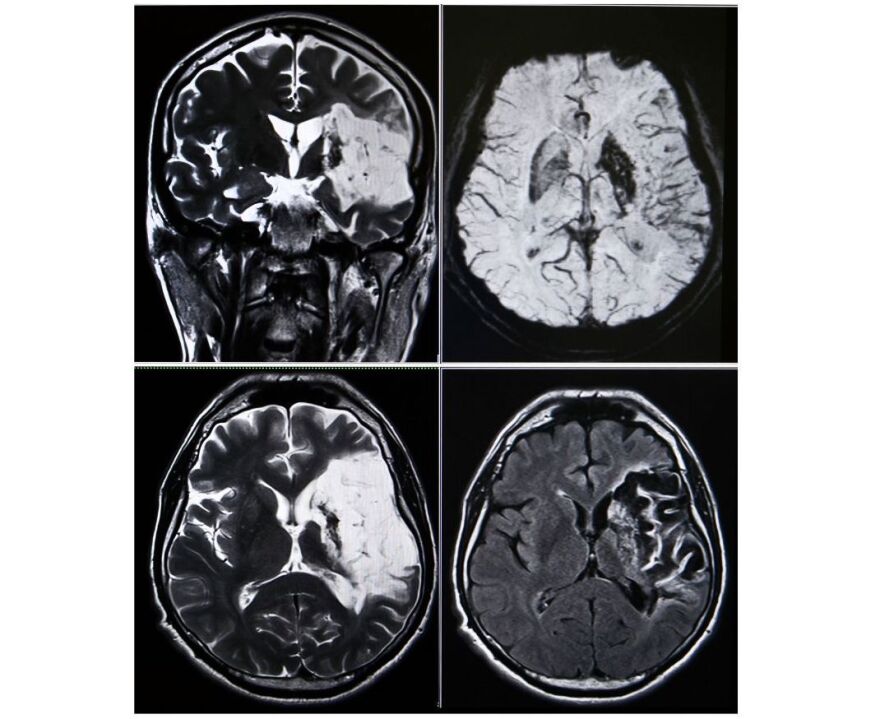

images of brain scans indicating stroke

Understanding stroke: causes, symptoms, treatment, recovery and support

Many people are unaware of the prevalence of strokes in younger and middle-aged people, which has been increasing in recent years. In fact, according to the World Stroke Foundation, one in four of us will have a stroke in our lifetime. We'll discuss signs and symptoms of strokes, prevention, and some of the advancements in stroke treatment.